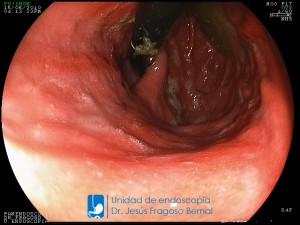

La Unidad de Endoscopía fue creada en 2002 por el Dr. Jesús Fragoso Bernal, es pionera en el estado por la utilización de la tecnología más avanzada, que nos permite ofrecer servicios integrales de diagnóstico y tratamiento para las enfermedades del aparato digestivo.